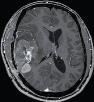

Machine learning has been widely adopted for medical image analysis in recent years given its promising performance in image segmentation and classification tasks. The success of machine learning, in particular supervised learning, depends on the availability of manually annotated datasets. For medical imaging applications, such annotated datasets are not easy to acquire, it takes a substantial amount of time and resource to curate an annotated medical image set. In this paper, we propose an efficient annotation framework for brain MR images that can suggest informative sample images for human experts to annotate. We evaluate the framework on two different brain image analysis tasks, namely brain tumour segmentation and whole brain segmentation. Experiments show that for brain tumour segmentation task on the BraTS 2019 dataset, training a segmentation model with only 7% suggestively annotated image samples can achieve a performance comparable to that of training on the full dataset. For whole brain segmentation on the MALC dataset, training with 42% suggestively annotated image samples can achieve a comparable performance to training on the full dataset. The proposed framework demonstrates a promising way to save manual annotation cost and improve data efficiency in medical imaging applications.

翻译:近年来,由于在图像分割和分类任务方面表现良好,医学图像分析广泛采用了机器学习。机器学习的成功,特别是监督学习的成功,取决于手动附加说明数据集的可用性。对于医疗成像应用来说,这种附加说明数据集不容易获得,需要大量的时间和资源来翻译附加说明的医学成像集。在本文件中,我们建议为大脑MR图像建立一个高效的注释框架,为人类专家提供信息性样图像,供人类专家作说明。我们评估了两种不同的大脑图像分析任务的框架,即脑肿瘤分割和整个大脑分割。实验显示,对于BRATS 2019数据集的脑肿瘤分割任务,培训一个只有7%的附加说明图像样本的分解模型,其性能与全数据集培训的性能相当。对于MALC数据集的整个大脑分割,用42%的附加说明性图像样本进行的培训,可以实现与全数据集培训的类似性能。拟议的框架展示了节省人工注解成本和提高医疗成像应用数据效率的有希望的方法。